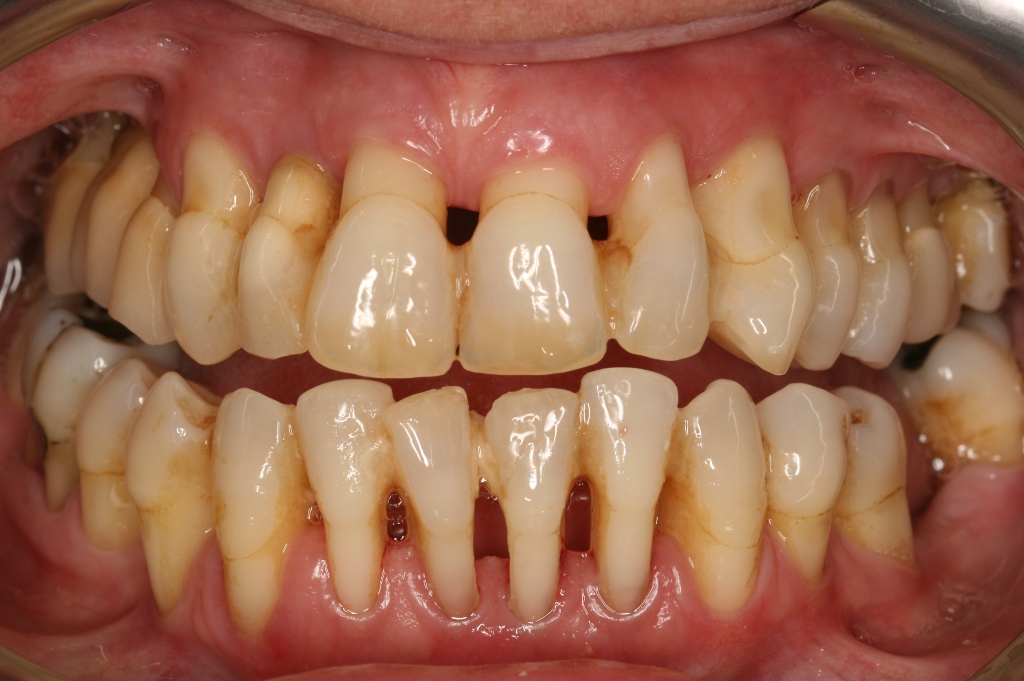

7. Periodontitis y pérdida de hueso

Hay infinidad de estudios que demuestran la relación existente entre las enfermedades periodontales y la osteoporosis.

Durante la menopausia, estos problemas se agravan, ya que la reabsorción de hueso que afecta normalmente a todo el organismo afecta de igual manera a la boca.

Al mermarse el hueso maxilar, está en riesgo la supervivencia de los dientes, éstos pierden el soporte sobre el que se sostienen.